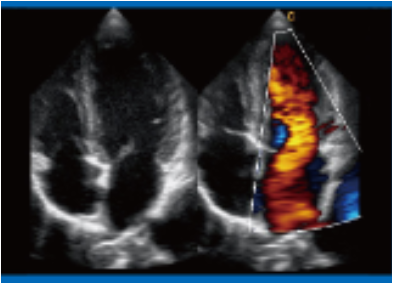

Примеры изображений:

Эхокардиография, 4-х камерная позиция, В/ВС-режим

Эхокардиография, 4-х камерная позиция, В/ВС-режим